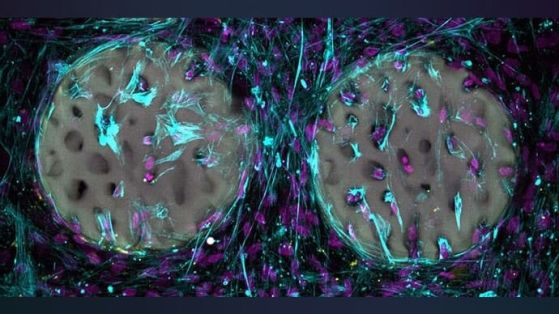

Костнообразуващите клетки (лилаво) са колонизирали костна структура на хидрогелна основа и произвеждат колаген (светлосиньо). Кредит: Xiao-Shua Qin / ETH Zurich